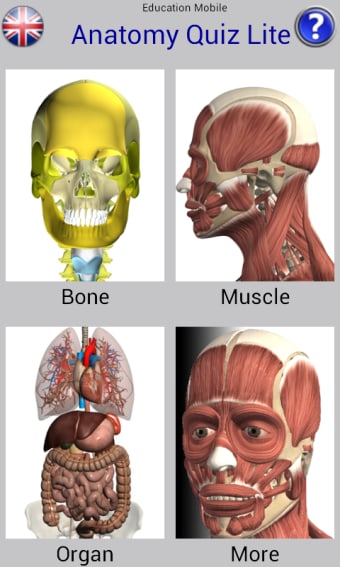

Anatomía Quiz Gratis: Una aplicación completa para aprender anatomía humana.

Anatomy Quiz Free es una aplicación de Android de Education Mobile que ofrece una amplia gama de cuestionarios para ayudar a los usuarios a aprender anatomía humana. La aplicación cuenta con más de 500 cuestionarios que ponen a prueba tu capacidad para identificar la ubicación correcta de un objeto dado su nombre. Los cuestionarios se generan a partir de modelos de anatomía 3D virtuales, lo que los hace más atractivos e interactivos. La aplicación es gratuita y no hay versiones premium ni compras dentro de la aplicación.